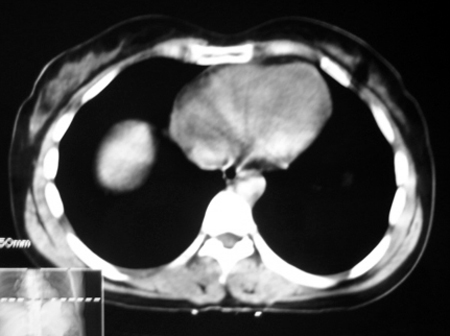

以下是引用bmw011在2009-4-23 13:28:00的发言:[br]考虑右肾包膜下血肿。

以下是引用卜一在2009-4-23 15:43:00的发言:[br]考虑右肾包膜下血肿,不排除占位病变伴出血可能,建议进一步检查。